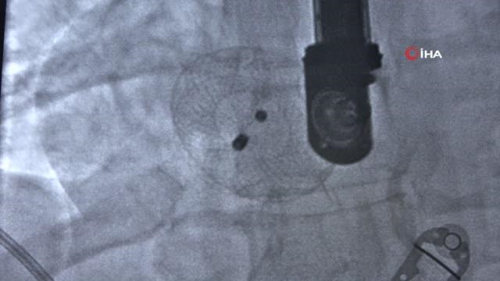

"Ameliyatsız sağlığına kavuştu" Müjgan Yıldırım, sağlığına kavuştuğunu belirterek, " Nefes darlığı ve kalp çarpıntısı şikayetlerim çok fazlaydı o yüzden kontrol amaçlı geldim. Doğuştan olan bir hastalıkmış ama 40 yaşından sonra kendisini gösteriyormuş. Ayaklarda şişlik, nefes darlığı yeni yeni olan belirtilerdi. Bu aşamadan sonra doktora gelip deliğin olduğunu görünce insan bir panik oluyor. Yakınlarım tanıyordu doktoru onların sayesinde geldim ameliyat oldum. Şimdi çok iyiyim. Anjiyo yöntemi ile kasıktan girilip deliği kapatmak için kalbe metal takılıyor" dedi.

"Delikler kapatılmazsa yaşam süresi kısalıyor" Kardiyoloji Uzmanı Dr. İsmail Erdoğu, kalpte ki deliklerin kapatılmadığı takdirde bu insanların kendi yaş gruplarına göre daha az yaşadığını ifade ederek, "Bize geldiğinde ultrason ile baktık ve kalbinde delik olduğunu gördük. Bu delik doğuştan olan ama geç fark edilmiş bir delikti. Yaklaşık 11 milimetre kadardı. İki alternatif vardı biri açık ameliyat ya da anjiyo altında kasıktan girerek bu deliği kapatmaktı. Biz bu deliği anjiyo altından girerek kesiksiz bir şekilde ameliyatsız kapattık. Hastamız gayet sağlıklı. Sadece bir gün yatırdık. Taburcu edeceğiz. Günümüz teknolojisi ile ameliyatlar anjiyo altında rahatlıkla yapılabiliyor ve ameliyat olmaya gerek kalmıyor. Biz 2 kardiyolog 1 anestezi uzmanı ve KVC' nin (Kalp ve Damar Cerrahisi) bu ameliyattan haberi vardı. Çünkü olumsuz durumlarda müdahale için ekibin hazır olması gerekiyor. Delikler kapatılmadığı zaman bu insanlar kendi yaş gruplarına göre daha az yaşıyorlar ve son yılları kalp yetmezliği ile mücadele ederek çok konforsuz geçiyor. Yaklaşık olarak kalp delikleri yüzde 1 ile yüzde 3 arasında görülüyor. Ama bu tarzda büyük olanların sıklığı bin de 1-2 civarında" şeklinde konuştu.